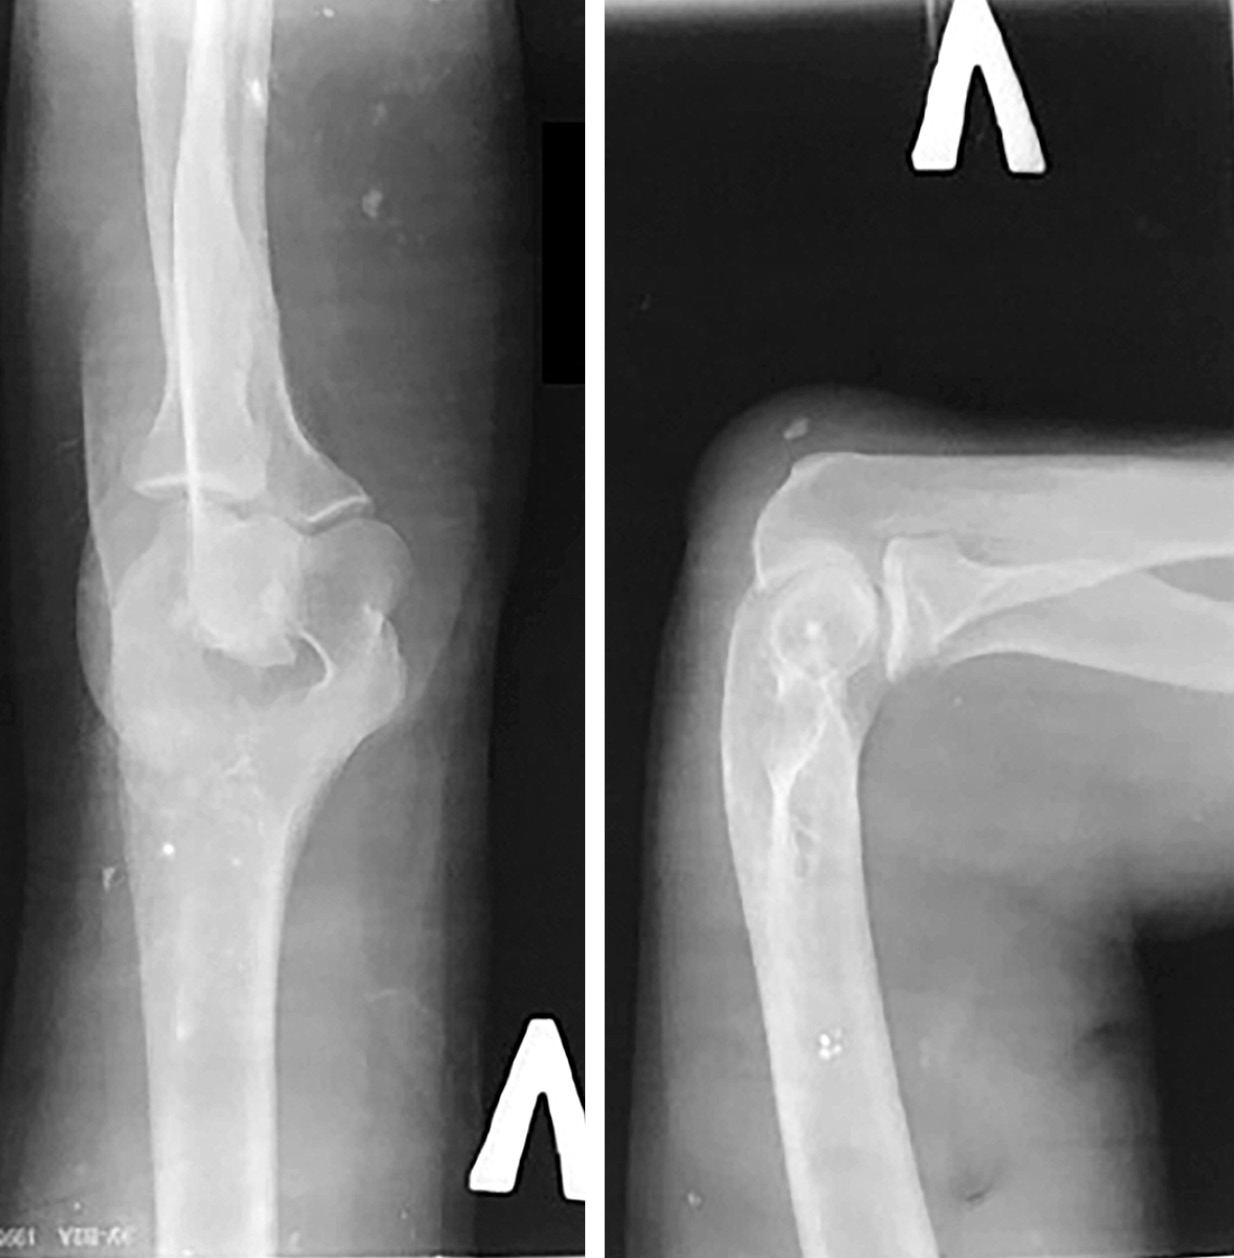

На рентгенограммах коленных суставов (рис. 8) травматический подвывих справа бедренной кости, большеберцовой с признаками двигательной нестабильности в суставе, хронический бурсит задне/наружного квадранта. Слева – средневыраженный артроз с ротационным подвывихом.

Рис. 8. Рентгенограмма обоих коленных суставов при поступлении, 2018 г.

На рентгенограммах локтевых суставов (рис. 9) – картина хронической стадии ДНОАП с обеих сторон.

Рис. 9. Рентгенограммы локтевых суставов при поступлении, 2018 г.